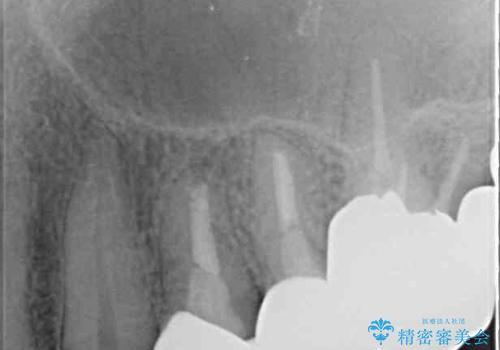

強い咬合力や磨きすぎなどにより、歯根が見えてしまったり、金属の縁が見えてしまったりし、審美障害を引き起こすことがあります。

歯根が変色してしまうと、歯肉越しに歯根の黒い色が透けてしまうことがあり、この点についてはどうにも施しようがないため、患者様には事前のご理解いただきました。